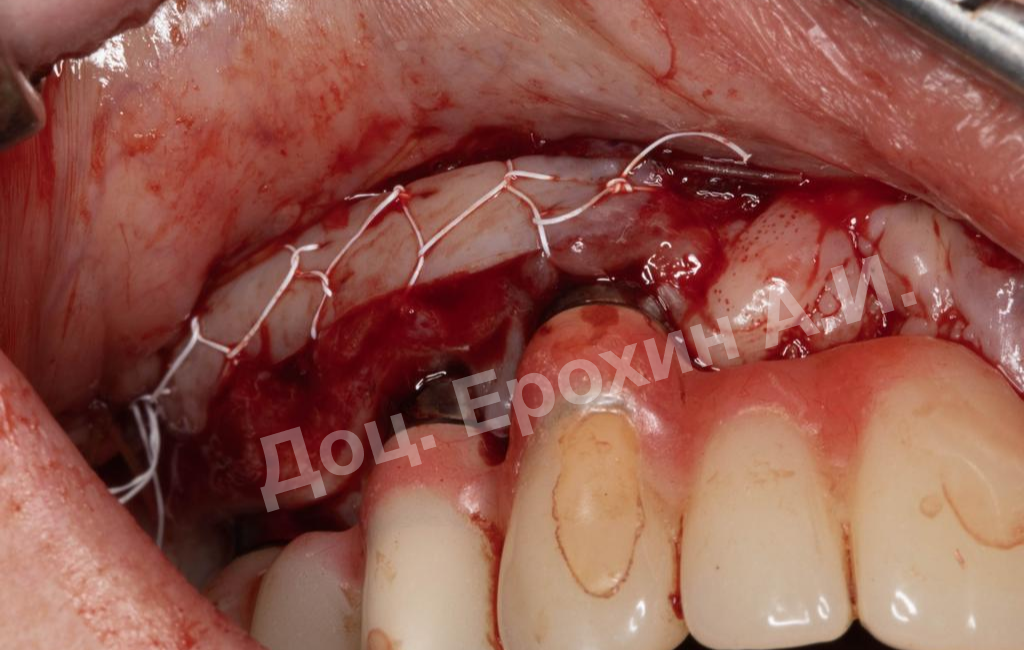

В результате, спустя 10 лет мы видим, что единственная часть десны в области имплантации, не затронутая рецессиями, — это зона, где была проведена трансплантация десневого фрагмента. С целью стабилизации имеющихся имплантатов на повторном приеме была проведена вестибулопластика по Кларку с фиксацией мягкотканных мукотомов, фрагментов эпителия с неба, зафиксированных швами.

В данном клиническом случае мы можем наблюдать эффект так называемого наползающего прикрепления (creeping attachment), когда десна после удаления момента натяжения начинает сама наплывать на ранее оголенные корни зубов и имплантаты.

На фото видно, что в первом сегменте с 2.5-3 мм оголение корня осталось меньше 1 мм, в области имплантата 21 рецессия самоустранилась, а в области имплантата 26 рецессия до операции была 4.5 мм, а после сократилась до 2 мм.